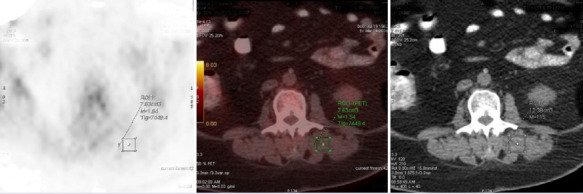

Objective: Sarcopenia is defined as an age-related loss of muscle quantity as well as quality. Also, it is associated with morbidity and mortality. Multiple myeloma (MM) has a unique aspect with its bone involvement. We aimed to investigate the effect of hematopoietic stem cell transplantation on sarcopenia in MM patients using both CT and metabolic compartment of F-18 FDG PET/CT.

Methods: Patients with MM who received first-line treatment and were eligible for autologous stem cell transplantation (ASCT) were included. FDG PET images before transplantation and after 120 days of ASCT were recorded.

Abstract Image